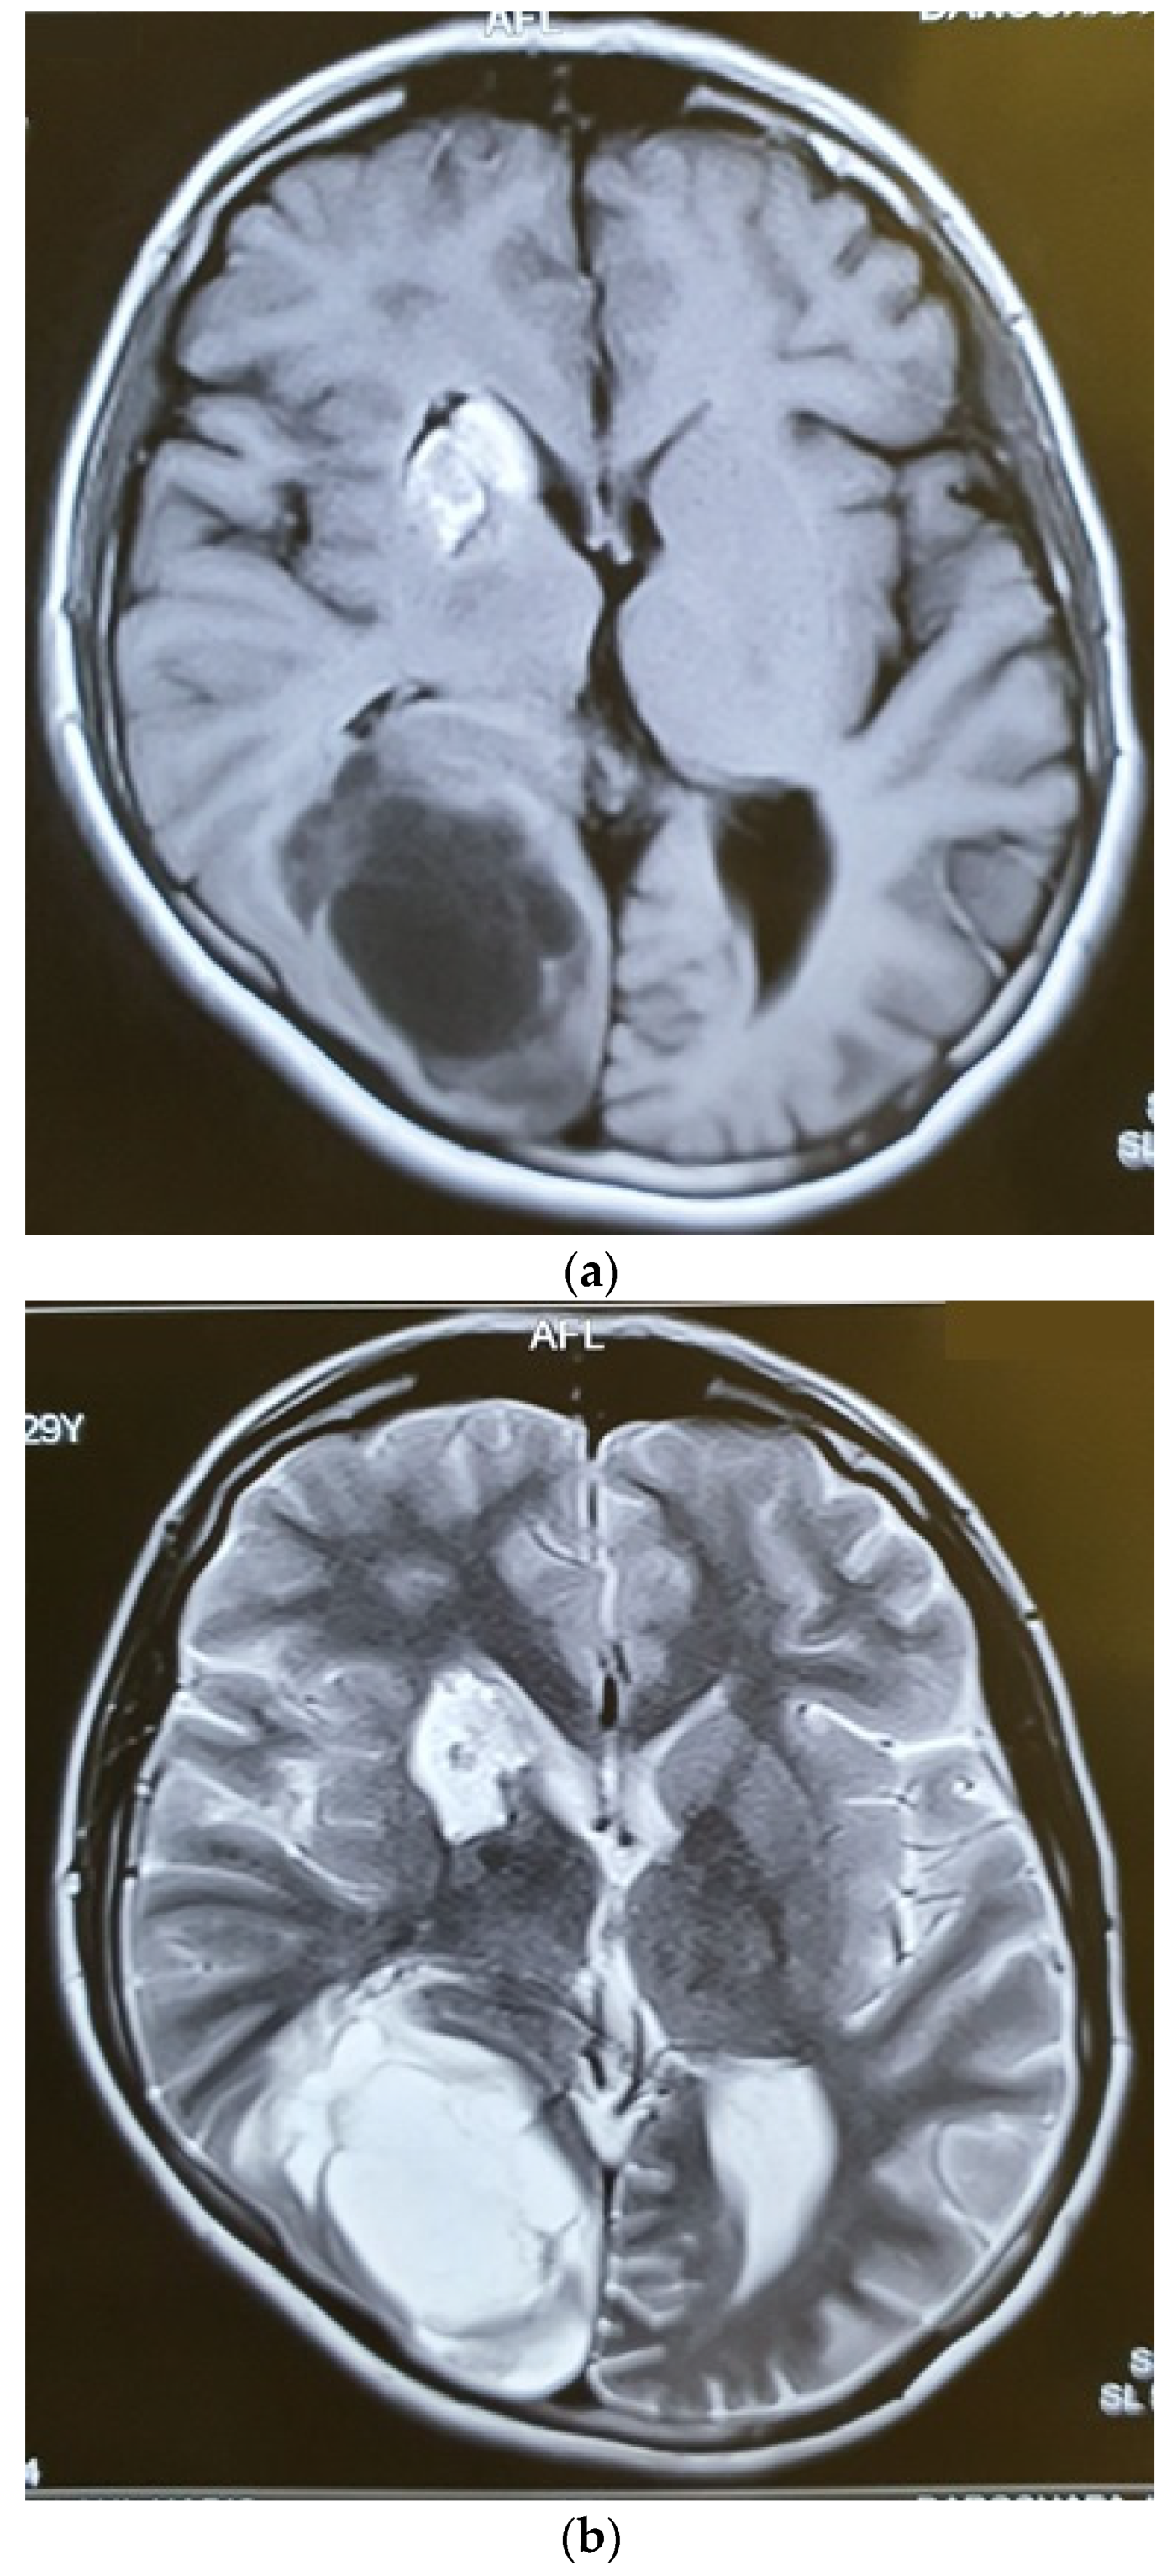

| The current case | 29, female | C2 | CD45, CD43, CD68, S100 | Surgery and radiotherapy | Brain metastasis after 9 months |